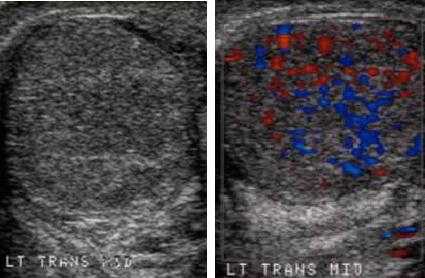

Мошонка и ее структуры кровоснабжаются через три основных сосуда - артерия семявыносящего протока, яичковая и кремастерная артерии. УЗИ с доплером позволяет увидеть кровоснабжение яичка и его придатка и оценить скорость и объем кровотока в тестикулярных сосудах. УЗИ с доплером помогает диагностировать ишемию на ранней стадии.

На рисунке справа показано нормальное кровоснабжение яичка.

УЗИ яичек при водянке яичка дает возможность диагностировать гидроцеле в виде анэхогенного образования внутри мошонки.

На ультразвуковом изображении слева визуализируется нормальное яичко, окруженное влагалищной оболочкой. Справа яичко окружено гидроцеле - между париетальным и висцеральным листками находится большое количество жидкости.